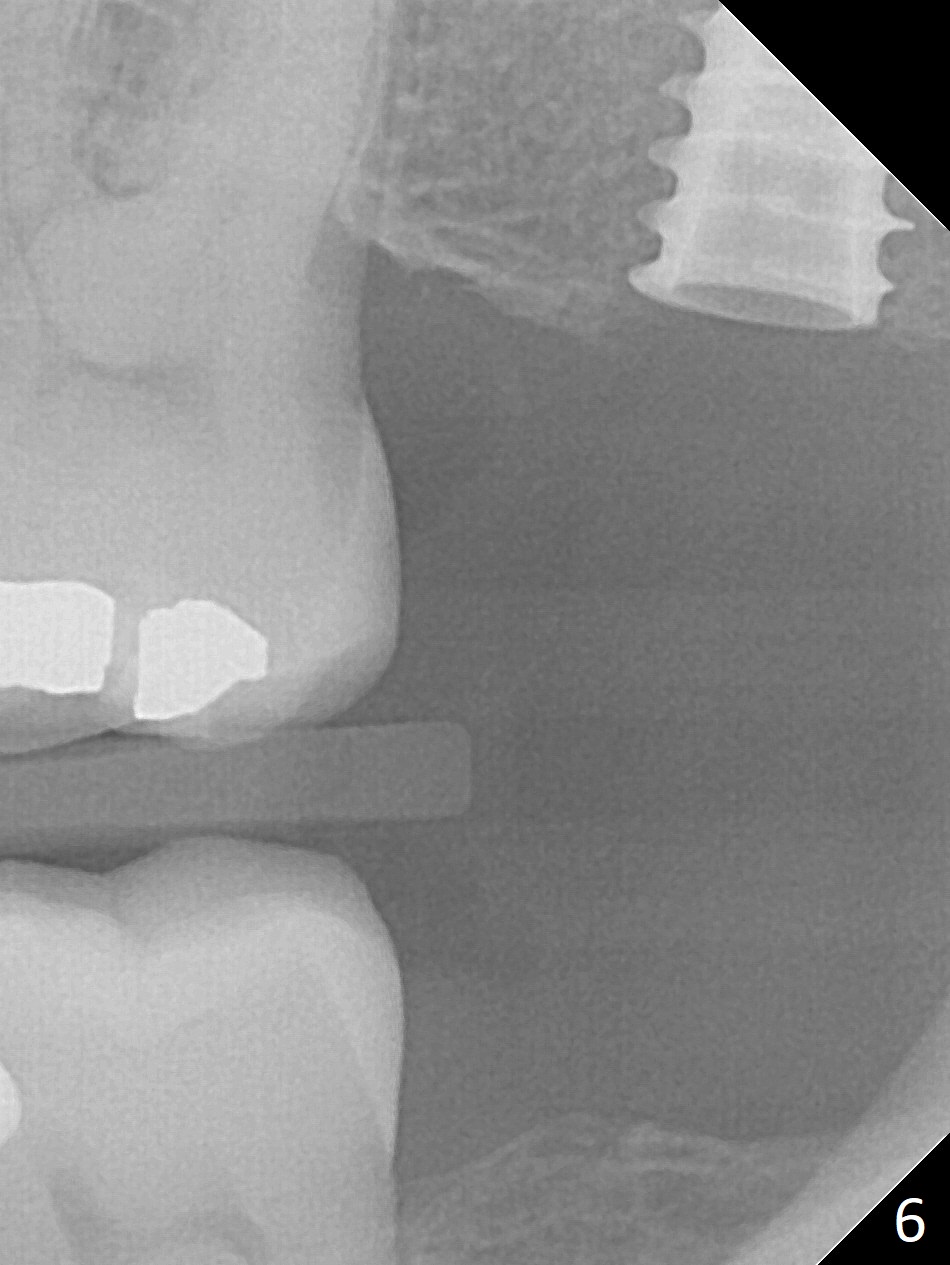

The ridge is pointed at the site of #15 (Fig.1). A 1.2 mm initial drill is used to start osteotomy for 10 mm, followed by an incision over the ridge mesiodistally for ~ 8 mm. After tapping the #15 C blade, the 1st Bone Expander 1.0/1.6 mm) is inserted for ~ 11 mm (Fig.2, 20 Ncm). Bone expansion continues until #4 Expander (2.4/3.7 mm, Fig.3). When 4x11 mm and 4.5x11 mm dummy implants are placed (Fig.4), insertion torque remains 20 Ncm. Following placing allograft with 3-4 amalgam carriers, a 5x11 mm IBS implant is placed with 20 Ncm (Fig.5,6). In fact the implant turns when an abutment is placed. When the implant is re-inserted, torque decreases to 10 Ncm. Instead a healing screw is placed. The low torque value is due to soft bone and failure to underprep. #4 Expander (Fig.3) seems larger than 4.5 mm implant (Fig.4). #3 Expander (1.7/3.1 mm) should have been used prior to definitive implant placement. The implant appears to have osteointegrated 3 months postop (Fig.7); impression is taken. The bone density at the crest increases 1.5 years post cementation (Fig.8 *, as compared to Fig.6), although there is mild bone loss. Implant placement should be deep when bone expansion is carried out. The tooth #14 develops a buccal fistula, corresponding to periapical radiolucency of the mesiobuccal root (Fig.9 white >). The abutment of #15 may be incompletely seated (black <). PA taken when RCT of #14 is finished does not show the incomplete seating of the abutment (Fig.10). Since there appears no history of abutment screw loosening, the abutment is not reseated when #14 is prepared for crown. Recall 3 years 7 months post cementation shows incomplete seating of the abutment (Fig.11 >). After crown proximal reduction (Fig.12 *) and clockwise turn of the crown, the abutment appears to be completely seated. When the case returns from lab, the separate crown and abutment cannot be connected to the fixture because of soft tissue adaptation and change in a month. The abutment is reseated to the fixture analog in the model and the crown is recemented with temp bond (in case of misalignment) while making sure that the crown has the best proximal contact with the neighboring crown. With the abutment and crown in a unit, it is much easier to reseat the abutment with normal proximal contact. The torque is 20 Ncm. The access hole is closed with Cavit.